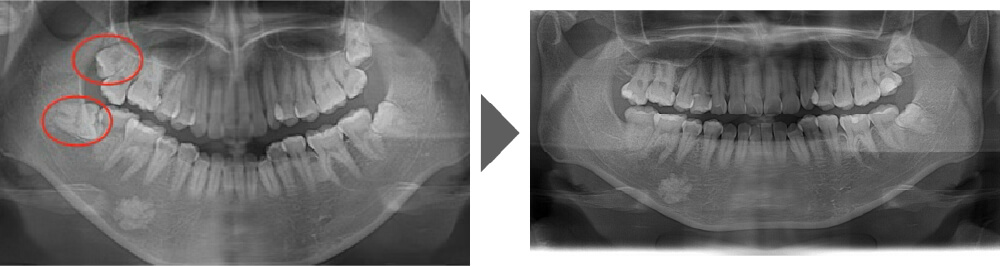

抜歯症例⑦

完全に生えているわけではなく、 向きも含めて難易度の高い抜歯です。 通常は1本60分要してもおかしくありません。 2本とも抜歯いたしました。

【抜歯所要予約時間】

1本30分

(麻酔の時間があるので処置自体はもっと短いです)